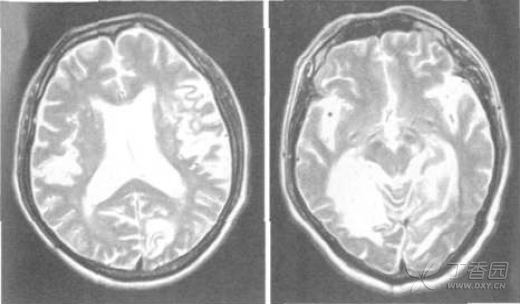

头颅CT示左侧大脑半球低密度影,右侧颞顶枕叶软化灶。诊断考虑定位于左侧大脑半球大脑中动脉与后动脉供血区,定性为缺血性脑血管病,首先考虑脑血栓形成。入院后血尿便常规、红细胞沉降率、血凝、血脂、血糖、电解质和肝肾功能等均正常。心电图示异常Q波。心脏超声示左室松弛性下降,颈动脉超声示双侧颈总动脉内膜毛糙。TCD示左侧大脑中动脉-颈内动脉分叉部伴杂音,脑动脉血流速度减低,弹性下降。头颅MRI示左侧基底节区和左侧颞枕叶急性脑梗死,右侧颞顶枕叶陈旧性脑梗死(图1)。视觉诱发电位结果正常。请眼科医师会诊,考虑患者色觉障碍为脑梗死引起,属后天性,查后天色觉障碍检查表(第V组)2004版:图99读为90,图60未能读,图266读为200,图928读为911,图68读为62,准确率为30%。